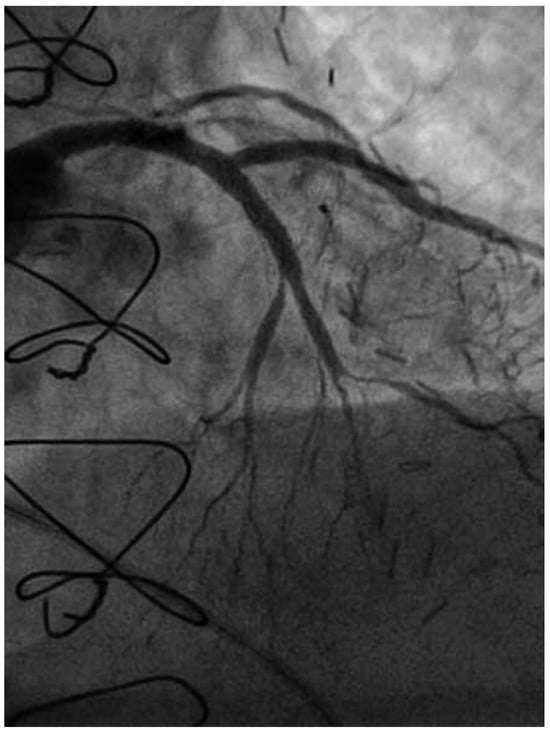

Following RA, both LAD and diagonal were wired with ease using separate Runthrough (Terumo, Japan) wires. Predilatation of both bifurcation limbs was undertaken using 1.5 × 15 mm Trek (Abbott) and 2.0 × 10 mm Sapphire (Orbus-Neich, Hong Kong, China) semicompliant balloons, which both expanded well at nominal pressure. Intending to perform an elective T-stent strategy, a 2.25 × 28 mm Promus Premier DES was deployed at 18 Atm in the diagonal branch, landing proximally at the ostium of this vessel (Figure 3). After removal of the diagonal wire, a 3 × 38 Promus Premier stent (Boston Scientific) was sited from the origin of the LMS across the first diagonal and deployed at 18 Atm (Figure 4). The diagonal branch was then rewired with the runthrough wire. A kissing inflation was performed at 12 Atm using a 3.5 × 12 Quantum (Boston Scientific) and 2.5 × 12 Sapphire noncompliant (NC) balloons in LAD and diagonal, respectively (Figure 5A). The proximal LAD and LMS were then optimised using the 3.5 Quantum NC (LAD) and a Hiryu (Terumo) 4 × 10 NC (LMS) balloons at 22 and 18 Atm, respectively (Figure 5B). The final angiographic result was excellent (Figure 6). Intravascular ultrasound of the LMS was not undertaken as angiographically the LMS stent already appeared completely expanded and oversized. We opted not to intervene in the ostial left Cx in order to best preserve the geometry of the LMS stent.

Figure 3. RAO 15°, cranial 40° view. The diagonal now stented with a Promus Premier 2.25 × 28.

Figure 4. LAO 30°, cranial 30° view. A Promus Premier 3.0 × 38 stent has been deployed from ostium of LMS across the diagonal.